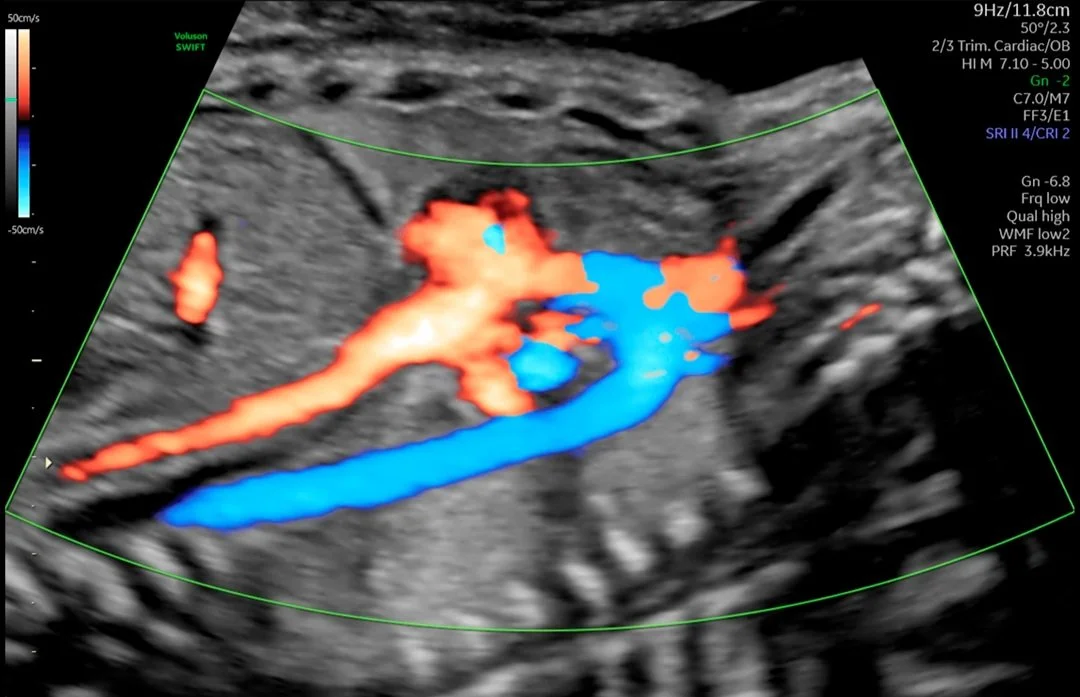

Obstetricia

Desde las primeras fases del embarazo hasta el nacimiento, la salud de la madre y el feto es su prioridad. Es por eso que nuestra prioridad es garantizar una adquisición de imágenes extraordinaria en todas las etapas del embarazo para explorar con confianza la anatomía del feto y detectar anomalías más rápida que nunca antes.